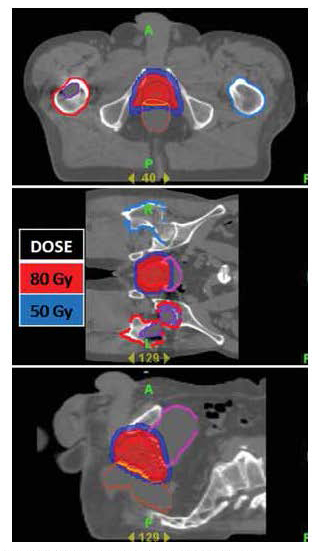

Radiotherapy (RT) is one of the established primary modalities for treating prostate cancer. Approximately 30% of all prostate cancer patients who are treated with curative intent receive RT, most with external beam radiotherapy, and a substantial proportion will be cured.[9][10] Studies have shown that IMRT/IGRT allows significant escalation of radiation dose with excellent biochemical control of disease with the same or less treatment-related morbidity.[11][12] With theTomoTherapy® Hi•Art® system, radiation is highly conformed to the prostate, minimizing dose to surrounding bowel, bladder and hips (Figure 7). Daily CT Image guidance ensures the prostate is exactly localized prior to treatment.

| Figure 7: A highly conformal radiation plan utilizing the TomoTherapy® Hi•Art® treatment planning software for a patient with early stage prostate cancer. In red, the high dose radiation precisely encompasses the prostate. There is a steep dose gradient (blue) surrounding the prostate. The dose of radiation delivered to the adjacent bladder and rectum is small, significantly reducing the potential for acute and/or chronic bowel or bladder complications. |